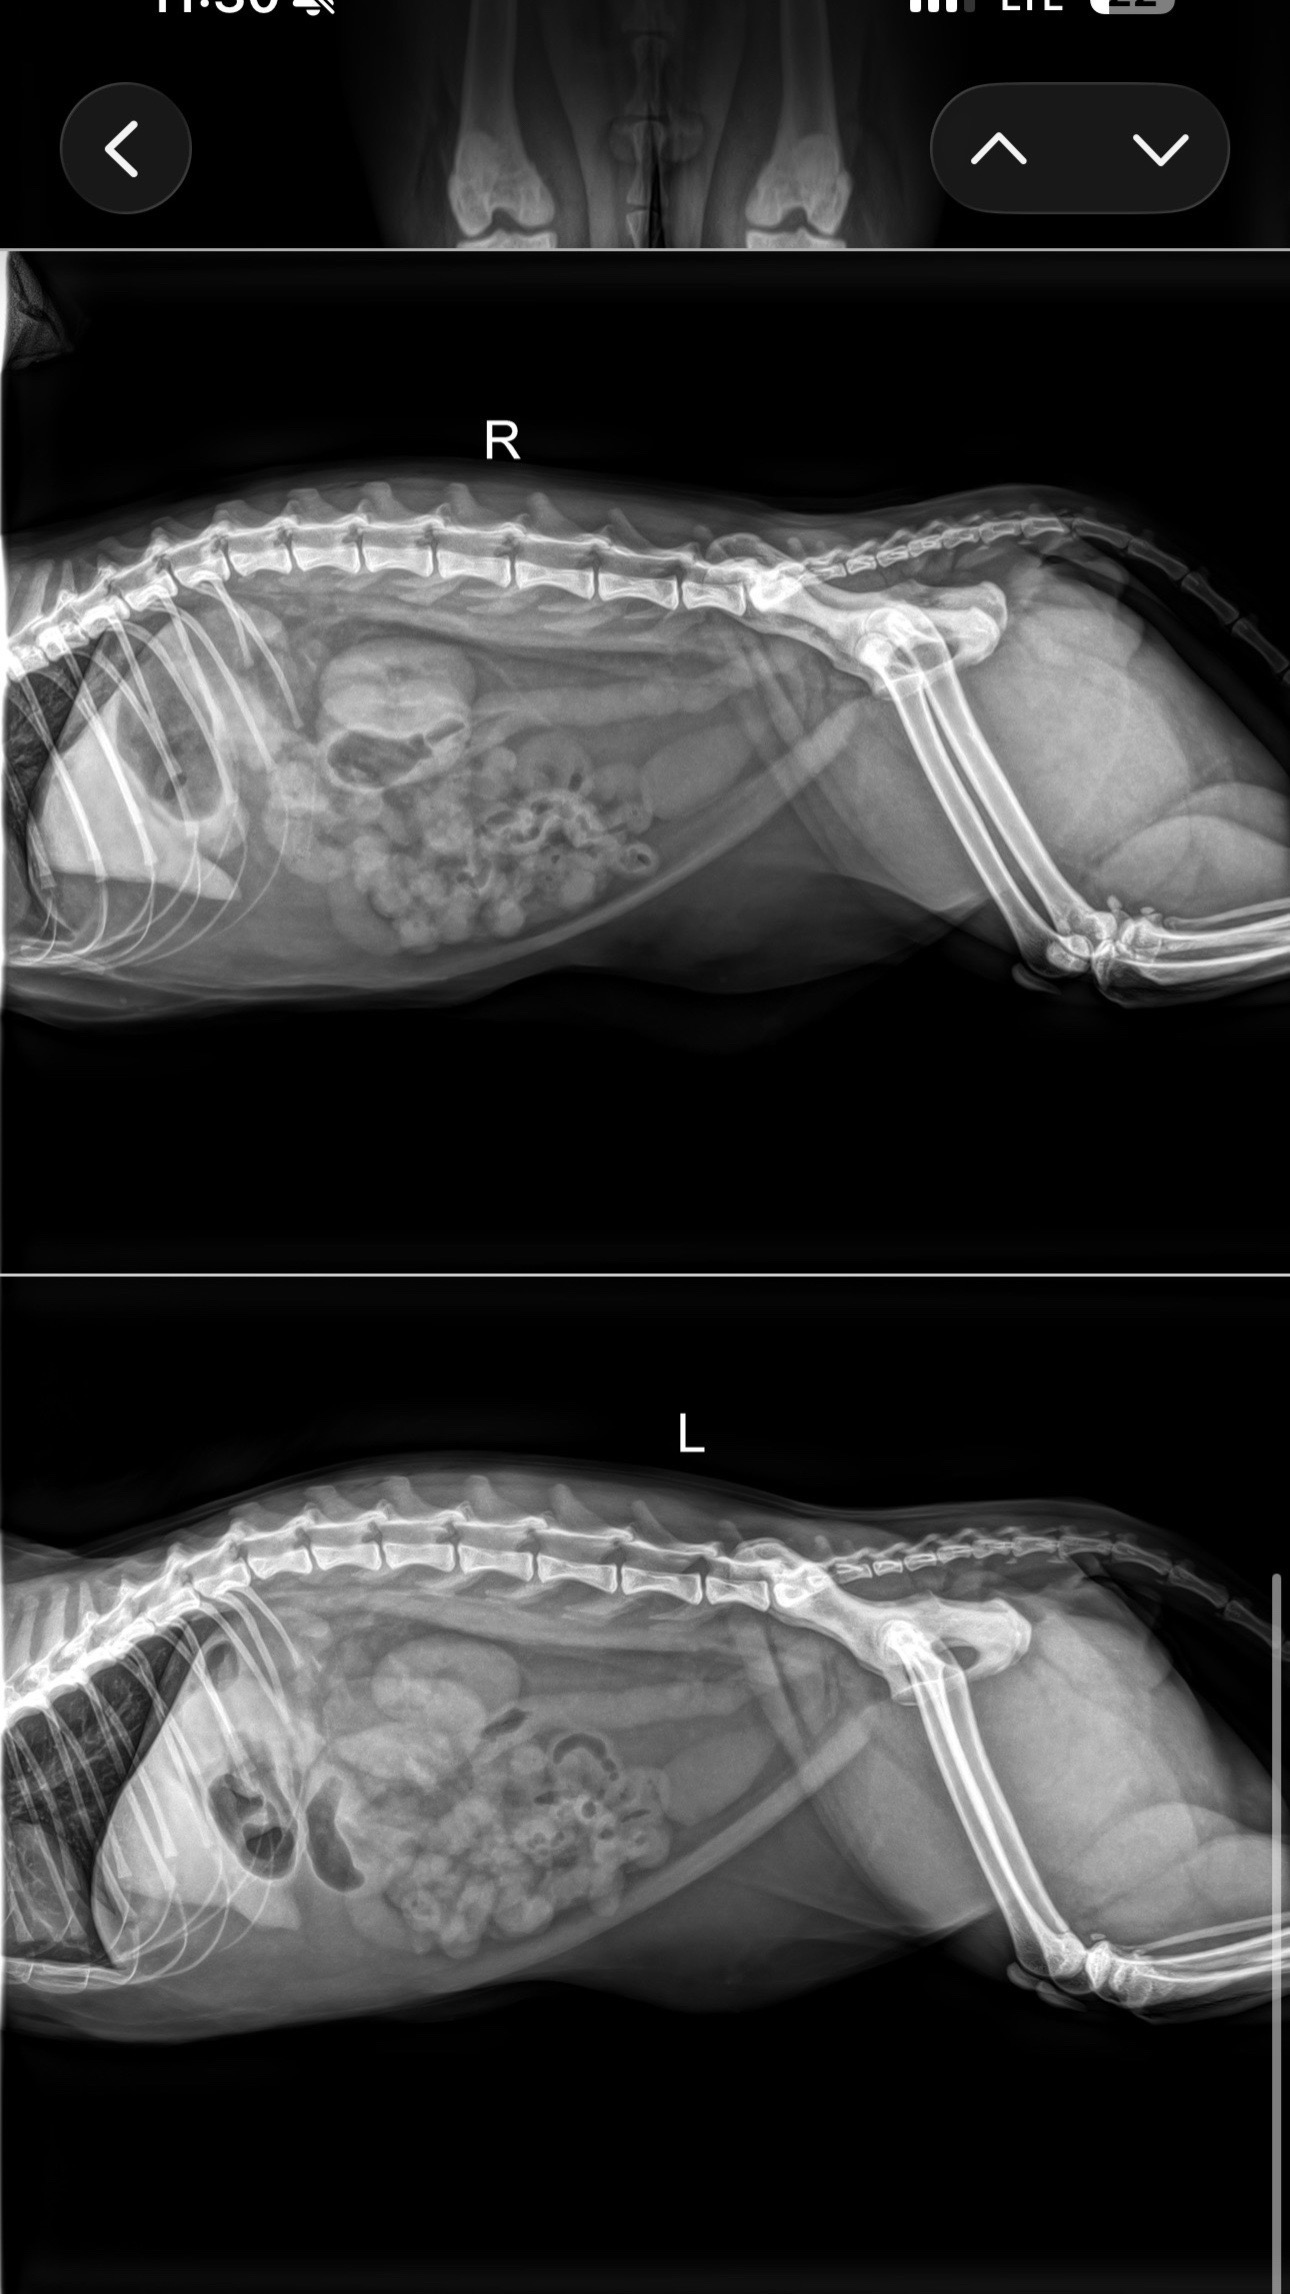

Hi everyone, I never thought I would be in this position, but I’m asking for help to save my baby, Blanco. Blanco is only 2 years old and is a very loved and spoiled indoor cat. He occasionally goes out to the patio to get some sun and fresh air. Unfortunately, he got into some fishing line and started chewing on it. I later noticed string coming out of his backside, and we rushed him to the emergency vet. We were told that the fishing line has caused his intestines to bunch up internally, and without emergency surgery, he will not survive. The cost of this surgery is far more than we can afford, even after trying every option available. We are doing everything we can right now, including transferring him to another hospital in hopes of getting financial assistance, but time is critical. Blanco is my baby and means everything to me. He just turned 2 on March 13 and has so much life ahead of him. I don’t want to lose him, and I don’t want to have to make the decision to put him down simply because we can’t afford his care. The funds raised will go directly toward his X-rays, hospitalization, emergency surgery, aftercare, and medications. If you are able to help in any way, even a small amount or simply sharing this, it would truly mean the world to us. If you’ve ever loved a pet, you know they are family, and I just want to give Blanco the chance to live the life he deserves. If you know me, you know how much my pets mean to me. They are my babies. Thank you so much from the bottom of my heart for any support, prayers, or shares.